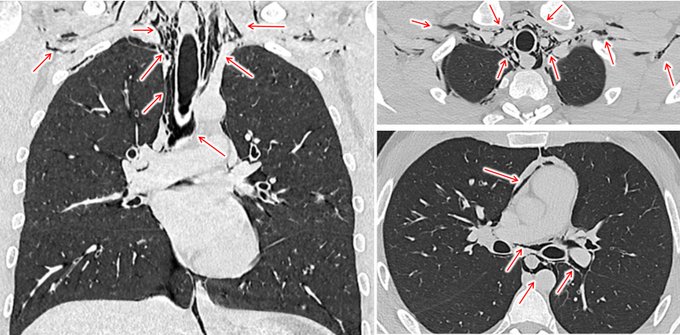

縦隔気腫とは、左右の肺の間、胸腔中央部にある「縦隔」という空間に、本来存在しないはずの空気が漏れ込み、貯留した状態を指します(胸部CTの赤矢印)。

胸部レントゲンでは添付画像のように見え(緑や青の矢印)、青矢印のように気管や大動脈弓などのラインが妙に鮮明に見えるのも読影ポイントのひとつです。

身体所見としては、心拍動と同期してザラザラ・バリバリとした摩擦音が聴こえる「ハマン徴候」、頸部や前胸部の皮下に“雪を握ったときのサクサク感”として触知される「握雪感」がとても有名です。